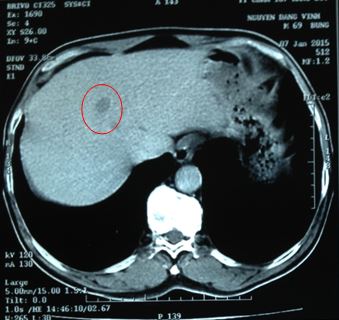

Trên phim chụp cắt lớp vi tính ổ bụng: nhu mô hạ phân thùy VIII có nốt đường kính 12 mm, giảm tỷ trọng trước tiêm, ngấm thuốc ít sau tiêm, nghĩ tới tổn thương thứ phát.

Hình 3: Hình ảnh chụp cắt lớp vi tính ổ bụng: khối tổn thương tại gan phải (vòng tròn đỏ)